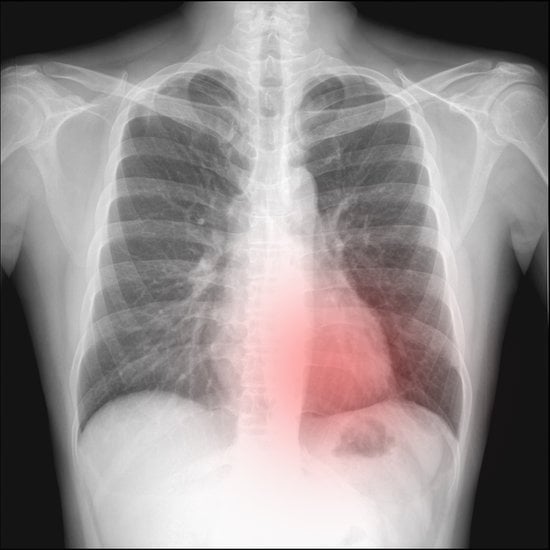

흉부 X선: 기흉 진단의 기본적인 영상 검사로, 폐와 흉막강 사이의 공기를 시각화하여 기흉의 존재 여부와 크기를 평가합니다.